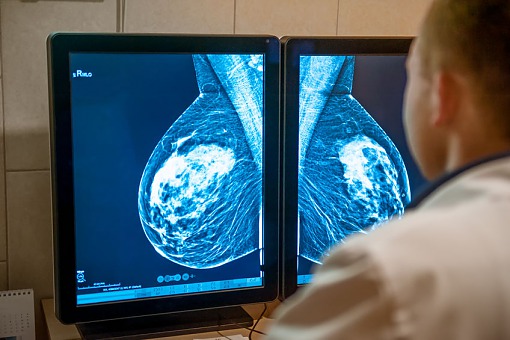

Rozpoczęcie mammografii od 40. roku życia zmniejsza ryzyko zgonu z powodu raka piersi

Jedną z kontrowersji dotyczącą mammografii jako badania przesiewowego jest wiek, w którym należy ją rozpocząć. Większość rekomendacji zaleca jej wykonywanie od 50. roku życia.

Najnowsze prospektywne badanie z randomizacją opublikowane w Lancet Oncology wykazało, że coroczna mammografia wykonywana pomiędzy 40. a 49. rokiem życia zmniejsza o 25% umieralność z powodu raka piersi w ciągu pierwszych dziesięciu lat obserwacji.

Aby uniknąć jednego zgonu z powodu nowotworu należy wykonać badanie u 1150 kobiet. W badaniu uczestniczyło ponad 160 tys. kobiet. U 53 tys. z nich przeprowadzono badanie przesiewowe, pozostałe stanowiły grupę kontrolną. U 18,1% kobiet, którym wykonywano mammografię, przynajmniej raz stwierdzono wynik fałszywie dodatni. 7% zgonów stwierdzonych podczas 23-letniej obserwacji spowodowanych było rakiem piersi. Nie wykazano spadku umieralności z powodu raka piersi w okresie powyżej 10 lat obserwacji.